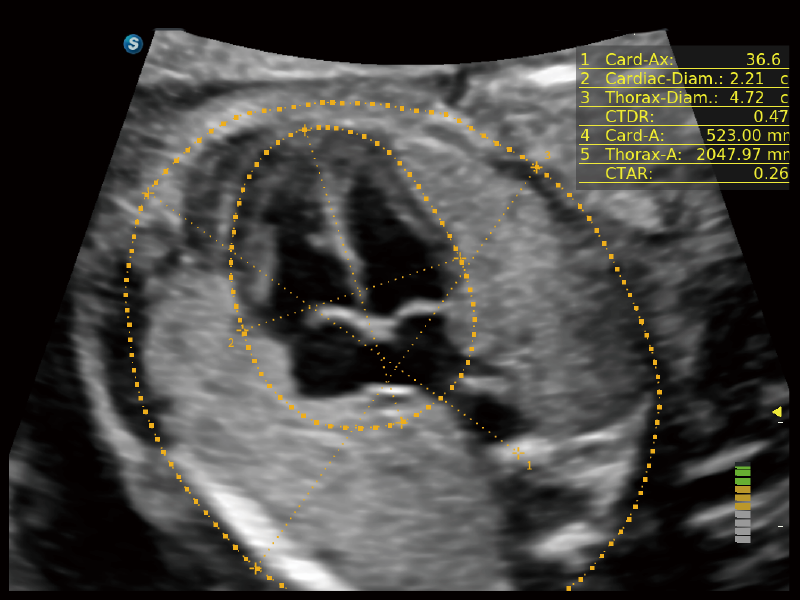

作为开立医疗全新打造的超高端旗舰超声产品,从探头抬起唤醒开启扫查到多维探头发射接收,通过先进的场成像发射、自适应聚合重建等技术,基于RF Data原始射频数据在图像生成、高端功能等方面实现突破,为妇产科、儿科提供全方位临床解决方案。

丰富的血流动力学检测技术,可在不同医疗场景中高效捕捉血流信号,助力临床诊疗。

在传统血流的基础上优化扫查和算法策略,能够更好的抑制组织信息,提炼红细胞运动信息,得到更高帧频,高灵敏度和分辨率的血流信号,还原更真实的血流动力学。